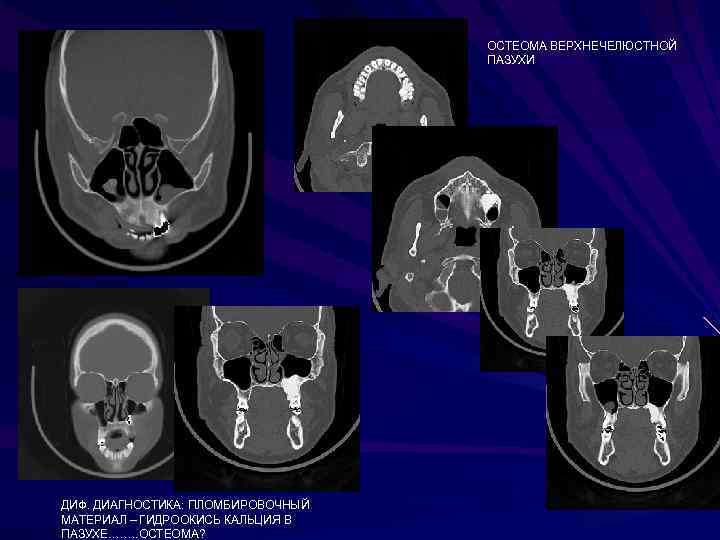

ОСТЕОМА ВЕРХНЕЧЕЛЮСТНОЙ ПАЗУХИ ДИФ. ДИАГНОСТИКА: ПЛОМБИРОВОЧНЫЙ МАТЕРИАЛ – ГИДРООКИСЬ КАЛЬЦИЯ В ПАЗУХЕ……. . ОСТЕОМА? ОСТЕОМА ВЕРХНЕЧЕЛЮСТНОЙ ПАЗУХИ ДИФ. ДИАГНОСТИКА: ПЛОМБИРОВОЧНЫЙ МАТЕРИАЛ – ГИДРООКИСЬ КАЛЬЦИЯ В ПАЗУХЕ……. . ОСТЕОМА?